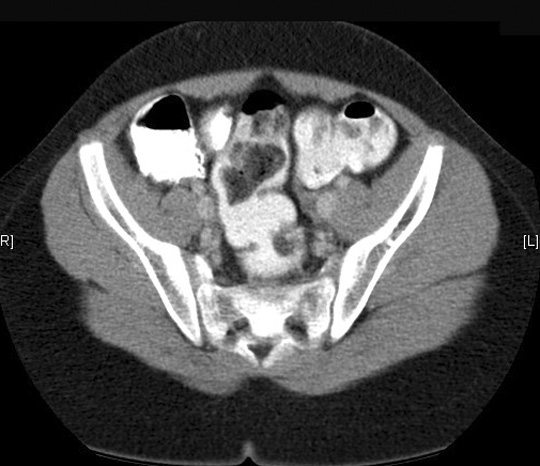

Note the rectosigmoid. Click the image for labeling.